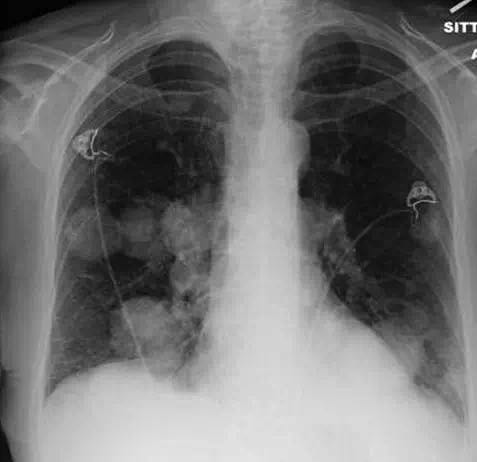

女,62岁,无显著既往史,在家中发现无意识而送医。患者进行紧急插管并就诊于急诊。检查发现患者有肾功能衰竭合并高血钾。胸部X线(图1)显示多发大的结节,高度提示肺转移。胸部(图2)、腹部和骨盆(图3)CT扫描显示毗邻膀胱的盆腔有大肿块,伴双侧肾积水,并有多发较大的空洞肺结节。盆腔肿块活检确诊为高度病变的膀胱移性细胞癌。遗憾的是,病人不接受包括化疗在内的任何侵袭性干预措施,并选择了临终关怀和姑息治疗。 诊断后1个月,患者去世。

肺部转移结节多呈大小不一、边界清楚的圆形结节,大小不同是由于瘤细胞转移到肺部的时间不同所致,边界清楚是由于充实性生长的癌结节与周围含气正常肺组织之间有良好的自然对比所致。

通常与弥漫性恶性肿瘤有关。 它们提示预后不良,但偶见报道预后良好的病例。这种典型征象见于肾细胞癌,也见于绒毛膜癌,子宫内膜癌,前列腺癌和一些胃肠恶性肿瘤。但是,与膀胱癌相关的征象罕见。